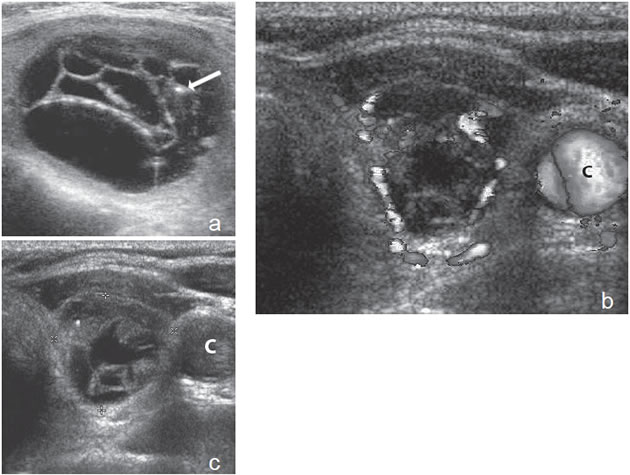

7. Invasión local y adenopatías

La extensión de la masa fuera de la cápsula, la infiltración de la tráquea o de los músculos pretiroideos es muy sugerente de malignidad (Figura 15a). Asímismo, la presencia de adenopatías con características típicas, debe hacer sospechar que el nódulo tiroideo es maligno. Los cánceres papilares de la tiroides son propensos a dar metástasis precozmente a los linfonodos cervicales y hasta la mitad de todos los pacientes pueden presentar adenopatías concomitantes. En 15% de los pacientes, el único signo de un cáncer tiroideo papilar oculto puede ser la detección de adenopatías. La mayoría de las metástasis ocurren ipsilateralmente al tumor primario en los grupos III y IV de la cadena yugular interna y del grupo VI del compartimiento central. En la ecografía, los linfonodos metastáticos pueden tener una forma redondeada o globular, una arquitectura con elementos sólidos o quísticos, con o sin microcalcificaciones y pérdida del hilio (Figura 15b y c). El “Doppler color” puede demostrar vasos capsulares de distribución caótica en reemplazo de los vasos hiliares normales (Figura 15d). Las adenopatías hiperecogénicas son sospechosas de cáncer papilar (Figura 16a). Los linfonodos normales en algunos grupos como el VI y el VII no se ven ecograficamente, de manera que si se hacen visibles, en el mismo lado del tumor, independiente del tamaño que tengan hay que considerarlos como adenopatías metastásicas (Figura 16b)

Figura 15. a) Cáncer papilar sólido de bordes lobulados (flechas) que muestra una gruesa calcificación central (flecha abierta) y múltiples

microcalcificaciones; b) Adenopatía cervical del grupo IV del mismo paciente (figura 15 a), hiperecogénica, con elementos quísticos (flecha

blanca) y microcalcificaciones agrupadas (flechas negras), típica de cáncer papilar; c) Adenopatías de grupo IV de un cáncer papilar, de

forma redondeada, hiperecogénicas, con pérdida del hilio, una anterior a la arteria carótida común (flecha) y otra lateral a la vena yugular

interna (flecha abierta); d) Corte sagital de la adenopatía lateral de la imagen 15 c), que en “doppler color” muestra vascularización patológica

y pérdida del hilio.

La apariencia ecográfica de los linfonodos metastásicos puede ser distinta a las del tumor primario y mostrar elementos quísticos y microcalcificaciones en mayor proporción que en el primario. En pacientes más jóvenes, las adenopatías puramente quísticas son relativamente comunes y cuando son solitarias pueden simular un quiste branquial o un quiste del conducto tirogloso.